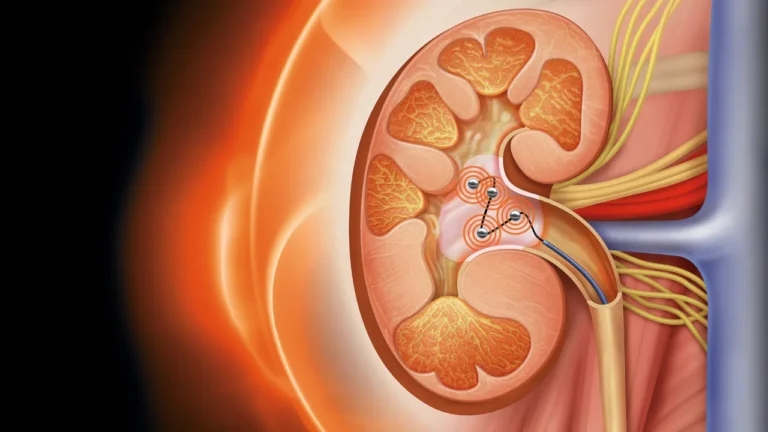

فناوری نوین «عصبزدایی لگنچه کلیه»؛ رویکردی جدید برای درمان هدفمند فشار خون بالا شرکت وِرو مِدیکال (Verve Medical) با معرفی فناوری نوآورانه «عصبزدایی لگنچه کلیه» (Renal Pelvic Denervation یا RPD)، گام تازهای در درمان بیماران مبتلا به فشار خون کنترلنشده برداشته است؛ رویکردی که میتواند رقابت جدیدی را در بازار درمانهای مداخلهای فشار خون…